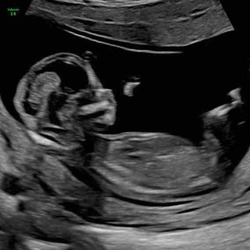

Hier ook een beetje hetzelfde verhaal. Bij echo 8w4d te horen gekregen dat het 2 weken achterliep en geen hartje, week later bevestigd en toen gestart met medicatie. Wel pas 4 dagen later op gang gekomen maar al bij al vielen de krampen en bloedverlies mee. Heb nu nog wel een klein beetje restweefsel wat bij de volgende menstruatie moet meekomen. Ik vind het emotioneel zwaarder dan fysiek…